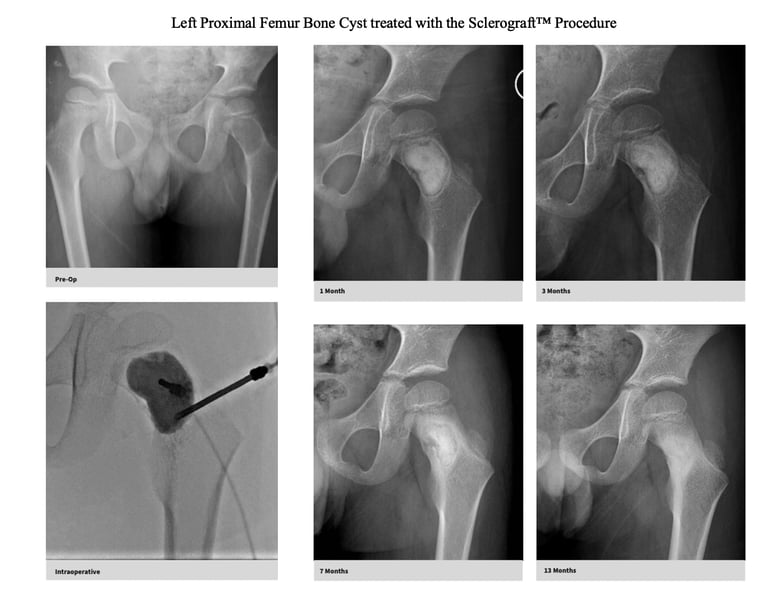

Gallery

Explore our educational resources and images